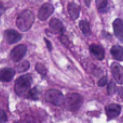

Figure 1: (a) H&E stained image; (b) H-component; (c) E-component; (d) fully annotated label; (e) Voronoi label; (f) cluster label; (g) inaccurate and incomplete area of (e) and (f), compared with (d). In (e) and (f), the green, red, and black pixels denote the label of positive, negative and ignored area, respectively. In (g), the yellow and blue masks denote the inaccurate and incomplete area, respectively.

Pathology slides contain abundant phenotypic information, and are widely used to study the manifestations of disease by analyzing cells or tissues under the microscope by pathologists [1]. Nuclei segmentation is a crucial step in pathology image analysis. The shape, size, density, and other indicators of the nucleus are related to the diagnosis and treatment of cancer [2, 3]. Different staining methods are used to increase the contrast between the different structures for their visual examination, where the most commonly used staining method for nuclei analysis is hematoxylin-eosin (H&E) staining, in which nuclei are stained blue-purple by hematoxylin (H-component), and cytoplasm and stromal matrix are stained red-pink by eosin (E-component) [4, 5], as shown in Fig. 1. Besides, with the advent of dedicated scanners, slices can be easily converted to digital pathology images, which are convenient to store on computers for further processing and analysis. Therefore, the wide availability of digital H&E stained pathology images greatly facilitates researchers in developing and validating advanced automatic pathological image analysis methods with nuclei segmentation.

Point annotation can be viewed as the most efficient manner for annotation, gaining increasing attention in cell/nuclei segmentation. Existing methods [23, 24, 25, 26] mainly encode the point annotation into coarse pixel-level labels, such as point distance maps [23], Voronoi labels [24], cluster labels [25], and pseudo edge maps [26]. As shown in Fig. 1, these methods typically inject the shape and texture prior knowledge of nuclei into coarse pixel-level label. For example, the points are assumed to be around the center and the nuclei shapes are nearly convex. Despite drastically reducing the annotation cost and alleviating the data-imbalance problem of point annotation, these methods still suffer from incomplete coarse labels and inaccurate boundary information, as illustrated in Fig. 1. Various methods have been proposed to eliminate the distraction induced by the coarse labels, which can be categorized into two classes: 1) multi-stage optimization to refine the segmentation in a bootstrapping way [23, 27, 24]; 2) adding additional constraints based on the local contrast between nuclei and their surrounding cytoplasm [25, 26]. However, the additional constraints could introduce inaccurate supervision, and a multi-stage learning strategy may suffer from error accumulation (i.e., the global optimum cannot be guaranteed).

In practice, directly using point annotation for the nuclei segmentation could suffer from the data-imbalance problem due to insufficient supervision information. To alleviate this issue, we adopt the Voronoi diagram [24] and the k𝑘k-means clustering method [25] to generate Voronoi label and cluster label, respectively. Specifically, for Voronoi labels, as shown in Fig. 1, the image is divided into convex polygons based on the point annotations with the assumptions that the point labels are at the nuclei centers and nuclear shapes are convex (even though these assumptions are not necessarily valid). For cluster labels, as shown in Fig. 1, we utilize the k𝑘k-means to obtain more supervision information of nuclei boundary and shape as follows. First, we calculate the distance maps from the point labels by performing distance transform between each pair of points. Second, the distance maps are combined with the original H&E stained images to conduct the k𝑘k-means clustering to divide all pixels into k=3𝑘3k=3 clusters: nuclei, background, and ignored area. The clusters that have maximum and minimum overlap with the point annotations are labeled as nuclei and background, respectively. The remaining one is the ignored class. The introduction of an ignored area allows pixels that cannot be easily determined as nuclei or background with certainty not be forced into either class, ensuring that the clustering can assign correct pixel labels as much as possible [27]. Third, several morphological operations are adopted to refine the cluster label, including connected domain labeling, scattered region removing, morphological opening operation, and binary hole filling.

As shown in Fig. 1, although part of the color information is lost in the obtained H-component image, the color contrast between the nuclear and non-nuclear regions is enhanced.

where visubscript𝑣𝑖v_{i} and cisubscript𝑐𝑖c_{i} denote the Voronoi label and cluster label of nuclei at the i𝑖i-th pixel, respectively; y=S(xh)𝑦𝑆subscript𝑥y=S(x_{h}) denotes the prediction of the segmentation network S𝑆S with H-component xhsubscript𝑥x_{h} as input; and ΩsubscriptΩ\Omega_{*} (i.e., ΩvsubscriptΩ𝑣\Omega_{v} or ΩcsubscriptΩ𝑐\Omega_{c}) is the set of non-ignored pixels. As illustrated in Fig. 1, the Voronoi label is used to supervise the network to separate overlapping nuclei, while the cluster label could provide coarse shape and boundary information for nuclei segmentation. In the following, we elaborate the co-training strategy to further provide supervision to the ignored area of the coarse cluster labels, denoted with the blue color in Fig. 1.